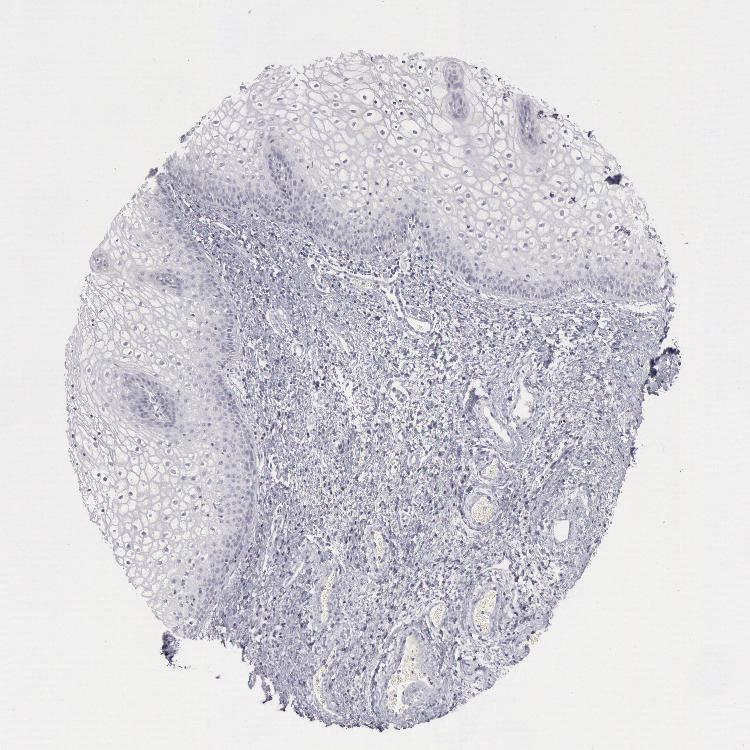

VAGINA - Antibody stainingi

Antibody staining in the annotated cell types in the current human tissue is reported as not detected, low, medium, or high, based on conventional immunohistochemistry profiling in selected tissues. This score is based on the combination of the staining intensity and fraction of stained cells.

Each image is clickable and will lead to virtual microscopy that enables deeper exploration of all samples and also displays staining intensity scores, fraction scores and subcellular localization as well as patient and tissue information for each sample.

Antibody CAB000136

Squamous epithelial cells Not detected